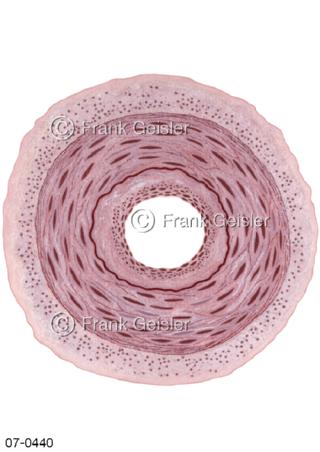

Bilder zu Herz, ein muskuläres Hohlorgan, das den menschlichen Körper durch rhythmische Kontraktionen mit Blut versorgt und dadurch die Durchblutung der Organe sichert, das Kreislaufsystem zeigt den Transport von arteriellem sowie venösem Blut durch das kardiovaskuläre System (Herz-Kreislauf-System), bestehend aus Blutgefäßen, Lymphgefäßen und dem Herz